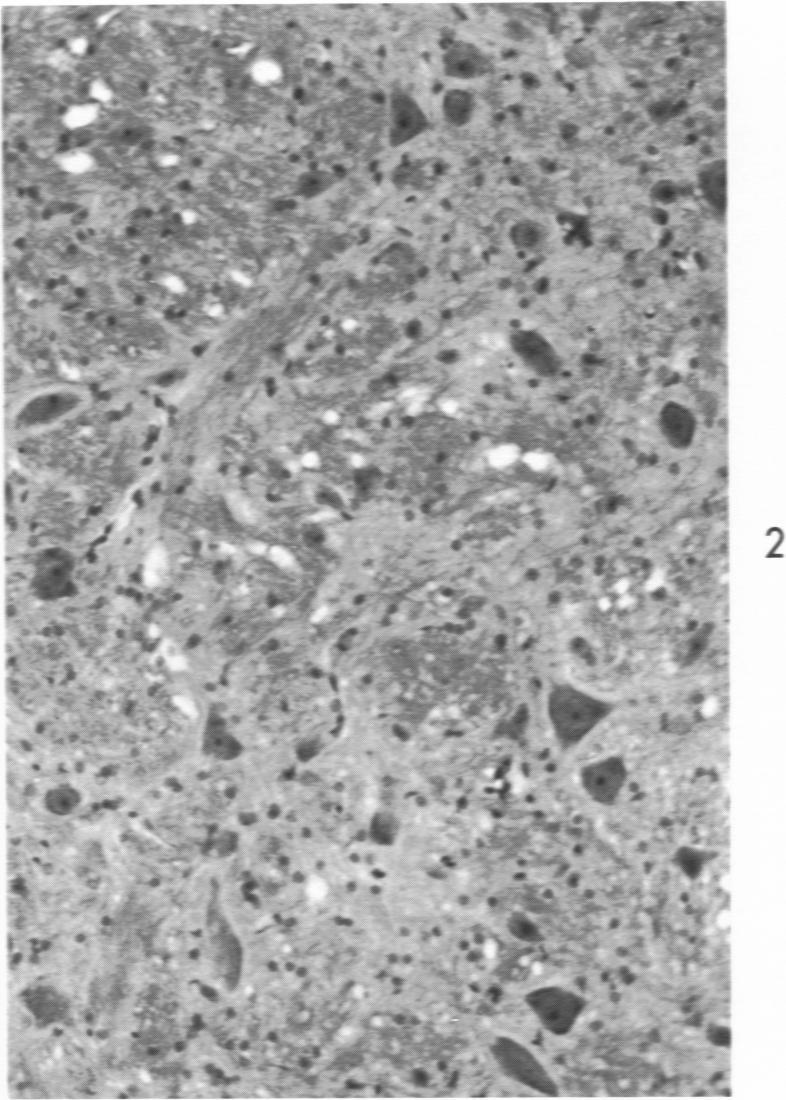

Effect of thiamine deficiency on the competence of the blood-brain barrier to albumin labeled with fluorescent dyes.

Am J Pathol. 1971 Jun;63(3):393-402.

PMID:5581230

原文链接:https://pmc.ncbi.nlm.nih.gov/articles/PMC2047487/